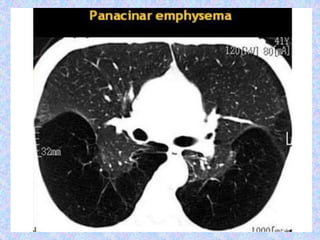

CT finding in emphysema is diagnosed by alveolar septal destruction and

airspace enlargement, which may occur in a variety of distributions.

Centrilobular emphysema is predominantly seen in the upper lobes with

panlobular emphysema predominating in the lower lobes. Paraseptal

emphysema tends to occur near lung fissures and pleura. Formation of giant

bullae may lead to compression of mediastinal structures, while rupture of

pleural blebs may produce spontaneous pneumothorax /

pneumomediastinum.

Abnormal chest X-rayfindings are usually not seen until COPD is severe. In this case, the X-ray may show: Flattening of the diaphragm, the large muscle that separates the lungs and heart from the abdominal cavity. Increased size of the chest, as measured from front to back. A long narrow heart. Abnormal air collections within the lung (focal bullae). On the lateral radiograph, a "barrel chest" with widened anterior-posterior diameter may be visualized. The "saber-sheath trachea" sign refers to marked coronal narrowing of the intrathoracic trachea (frontal view) with concomitant sagittal widening (lateral view). CT finding in emphysema is diagnosed by alveolar septal destruction and airspace enlargement, which may occur in a variety of distributions. Centrilobular emphysema is predominantly seen in the upper lobes with panlobular emphysema predominating in the lower lobes. Paraseptal emphysema tends to occur near lung fissures and pleura. Formation of giant bullae may lead to compression of mediastinal structures, while rupture of pleural blebs may produce spontaneous pneumothorax / pneumomediastinum.